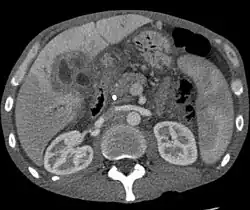

Ultrasound of the liver and biliary tree is often used as the initial imaging modality in people with suspected obstructive jaundice.[50][51] Ultrasound can identify obstruction and ductal dilatation and, in some cases, may be sufficient to diagnose cholangiocarcinoma.[52] Computed tomography (CT) scanning may also play an important role in the diagnosis of cholangiocarcinoma.[53][54][55]

While abdominal imaging can be useful in the diagnosis of cholangiocarcinoma, direct imaging of the bile ducts is often necessary. Endoscopic retrograde cholangiopancreatography (ERCP), an endoscopic procedure performed by a gastroenterologist or specially trained surgeon, has been widely used for this purpose. Although ERCP is an invasive procedure with attendant risks, its advantages include the ability to obtain biopsies and to place stents or perform other interventions to relieve biliary obstruction.[12] Endoscopic ultrasound can also be performed at the time of ERCP and may increase the accuracy of the biopsy and yield information on lymph node invasion and operability.[56] As an alternative to ERCP, percutaneous transhepatic cholangiography (PTC) may be utilized. Magnetic resonance cholangiopancreatography (MRCP) is a non-invasive alternative to ERCP.[57][58][59] Some authors have suggested that MRCP should supplant ERCP in the diagnosis of biliary cancers, as it may more accurately define the tumor and avoids the risks of ERCP.[60][61][62]